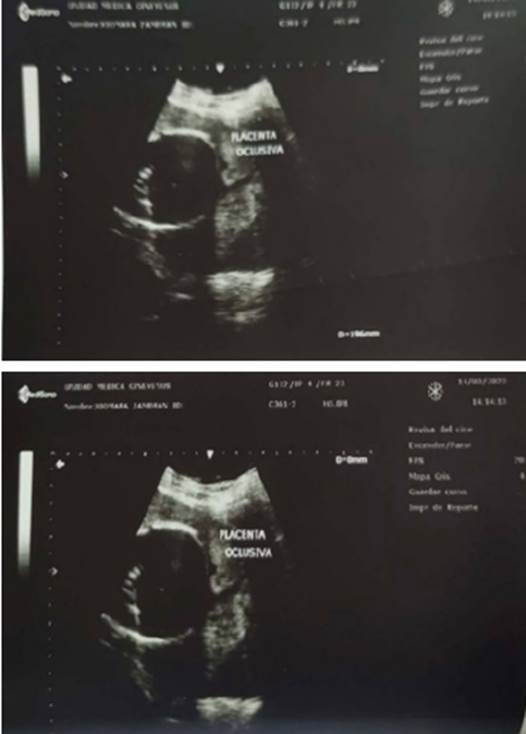

Figura 3 Reporte ecográfico de la paciente a las 27 semanas + 1 día de gestación por biometría fetal. Imagen ecográfica por vía transvaginal en plano sagital, donde se observa la placenta insertada en el segmento uterino inferior, delante de la presentación fetal, que ocluye por completo el orificio cervical interno.